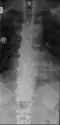

DISH in an 80 year old female, also with T11 fracture.

DISH is diagnosed by findings on x-ray studies. Radiographs of the spine will show abnormal bone formation (ossification) along the anterior spinal ligament. The disc spaces, facet and sacroiliac joints remain unaffected. Diagnosis requires confluent ossification of at least four contiguous vertebral bodies.[2] Classically, advanced disease may have "melted candle wax" appearance along the spine on radiographic studies.[13] In some cases, DISH may be manifested as ossification, or enthesis, in other parts of the skeleton.